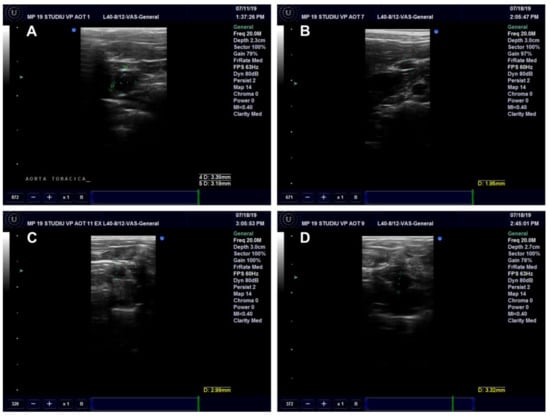

Ultrasound Examination of the Aorta and Left Ventricle